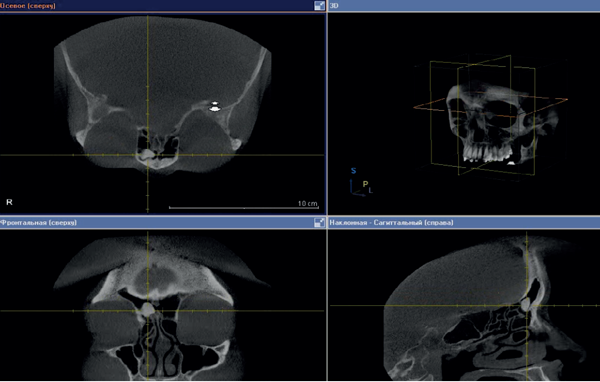

Figure 1: CT scan before surgery - right frontal sinus osteoma.

In January 2013, a 56-year-old woman presented at the ENT Department of First Pavlov State Medical University of St Petersburg, with discomfort in the right eye and right frontal sinus. These symptoms had occurred since 2011. The patient had been diagnosed with arterial hypertension. She had normal clinical analysis of blood and urine. Examination of the nose and nasopharynx with different endoscopes (0°, 30°, 45°) showed pink and moderate swelling nasal mucosa, nasal septum on midline. There was no pathological content on both sides of the nasal passages. CT scan of the paranasal sinuses revealed bone density tumours (1.0*1.5*1.0 cm) in the right frontal sinus with clear contours (Figure 1). The patient was advised to undergo surgical treatment.